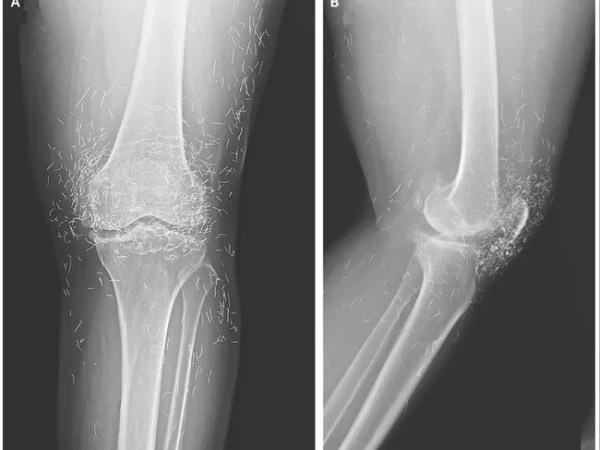

مذکورہ بالا تصویر ایک 65 سالہ خاتون کے گھُٹنے کے ایکسرے کی ہے جس میں دیکھا جا سکتا ہے کہ گھٹنے کے گرد سینکڑوں چھوٹے سونے کے تارموجود ہیں۔

بعد ازاں خواتین کے گھٹنے کا ایکس رے کیا گیا اور جو چیز سامنے آئی، وہ گھٹنے کے اندر سونے کے انتہائی باریک تار تھے۔ دراصل یہ تار اکیوپنکچر کے دوران باقاعدہ طریقے سے اندر چھوڑ دیے گئے تھے تاکہ جسمانی تحریکی اثر برقرار رہے۔

مزید برآں سونے کے تار چھوڑنے سے سیسٹ بن سکتے ہیں، یہ جسم میں حرکت بھی کر سکتے ہیں اور ایم آر آئی جیسی تصاویر بنوانے میں رکاوٹ یا خطرہ پیدا ہو سکتا ہے۔